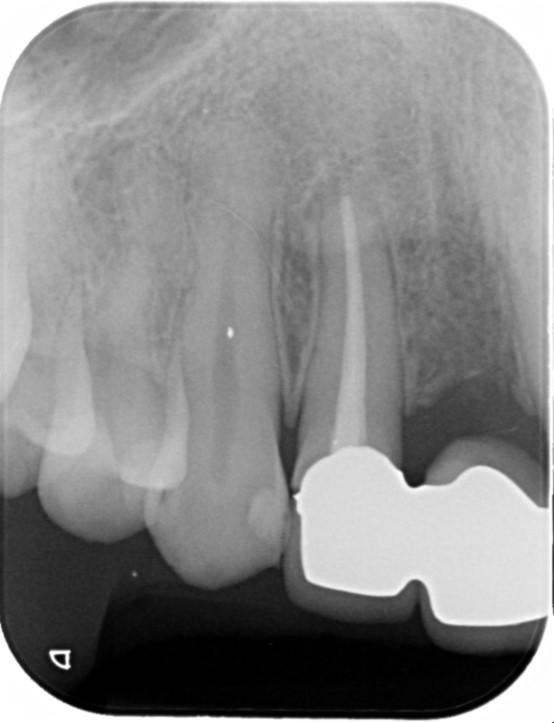

R5.8

右下4番破折の疑い

右下4番にフィステルが頻繁にできており、他院では抜歯のみと説明を受け、他の治療を検討できないかと当院にお越しになられました。

根管治療を数回行い、フィステルの出現は小さくなり頻度も減ったが抜歯が最善との判断に至りました。

抜歯をし、インプラントをご希望されていたのでしっかり5ケ月かけて経過を観察し、インプラントオペを行いました。